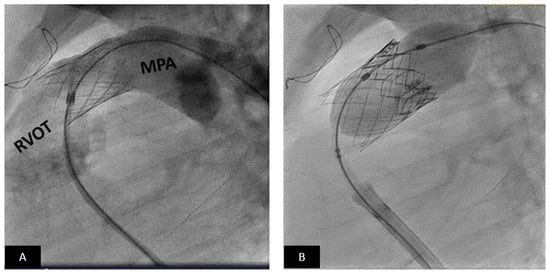

2.3. Transcatheter Valve Therapies

- Zahn, E.M.; Chang, J.C.; Armer, D.; Garg, R. First human implant of the Alterra Adaptive Prestent™: A new self-expanding device designed to remodel the right ventricular outflow tract. Catheter. Cardiovasc. Interv. 2018, 91, 1125–1129. [Google Scholar] [CrossRef] [Green Version]

- Bergersen, L.; Benson, L.N.; Gillespie, M.J.; Cheatham, S.L.; Crean, A.M.; Hor, K.N.; Horlick, E.M.; Lung, T.H.; McHenry, B.T.; Osten, M.D.; et al. Harmony Feasibility Trial: Acute and Short-Term Outcomes with a Self-Expanding Transcatheter Pulmonary Valve. JACC Cardiovasc. Interv. 2017, 10, 1763–1773. [Google Scholar] [CrossRef]